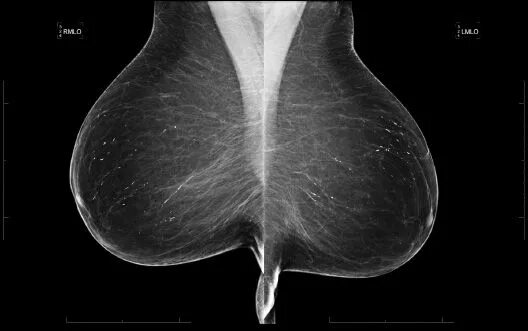

Susp c r